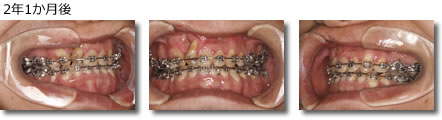

画像引用元:アイウエオ矯正歯科医院(https://www.aiueo-kyousei.com/c03/ortho_case_shingaku_top/ortho_case_shingaku_02)

メタルブラケットで歯の凹凸を矯正し、ゴムの力で下の歯を内側に矯正していきました。矯正期間は3~4週間に1回、保定期間は4~6ヶ月に1回程度の通院で治療。矯正には2年8ヶ月かかっています。